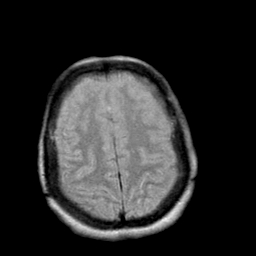

Creutzfeld-Jakob disease: proton density-weighted MR -- Slice #18

[Home][Help][Clinical] Slice 18